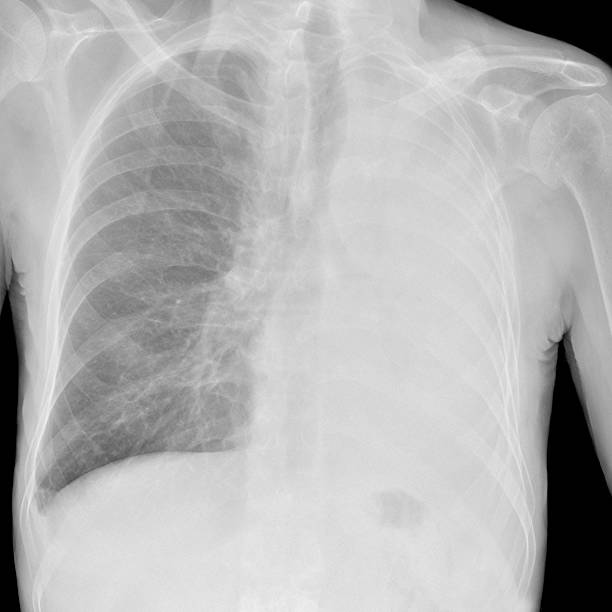

흉부 X선 검사

기흉이 의심되는 환자에게는 흉부 X선 검사를 실시하여 기흉이 있는지 확인할 수 있습니다. 이 방법은 비교적 쉽고 빠르게 기흉을 진단할 수 있습니다.